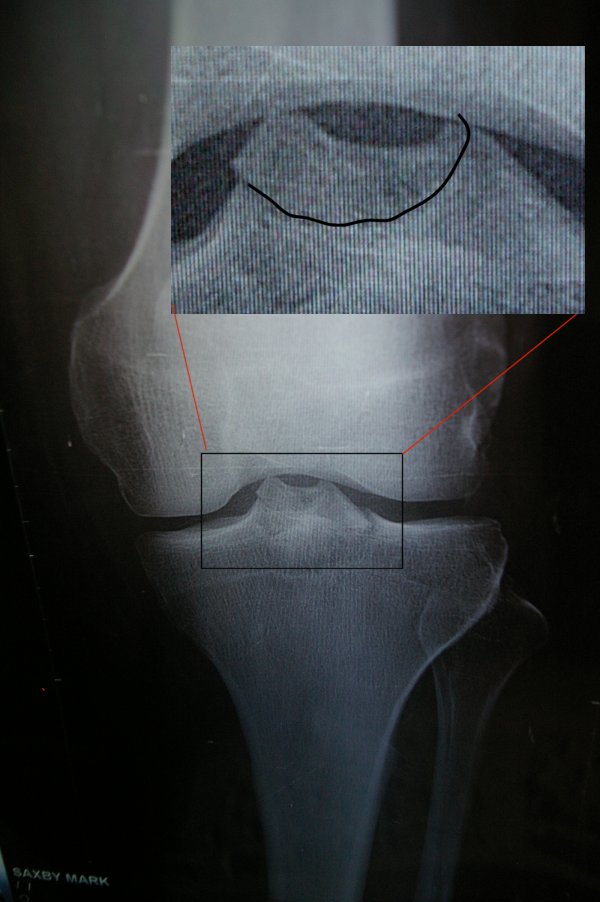

The doctor took one look at my swollen knee and said “That’s your skiing done for this week”. I was obviously disappointed, but not honestly surprised. He asked me some questions and manipulated the knee a bit and informed me that the ACL was ok (that was a big relief as some colleagues had spent many months recovering from damaged ACLs) and took a couple of X-rays.

A few minutes later he returned and asked how long I’d skied after the fall. I told him a couple of hours and explained where it had happened and that I’d skied back. He was amazed and said that he couldn’t believe that I could have skied at all. It seemed that I had fractured the ‘spine’ of my tibia in the knee joint. I was told that I needed a new brace (they no longer use the old plaster casts) to keep the leg fixed and that under no circumstances should I try and walk on it again without the aid of crutches.

He also prescribed daily injections to ward of any risk of thrombosis, anti-inflamatory tablets and some pain killers. He also stated that I would need to take an ambulance from the resort back to Geneva! Fortunately, I have good insurance, so I hope they’ll take care of all the costs eventually!

I have to visit a specialist when I get back to the UK, but the doctor suggested it may just need orthopaedic treatment to heal, rather than an operation and that it will probably take 6-8 weeks.

Above : My x-ray taken in Val Thorens